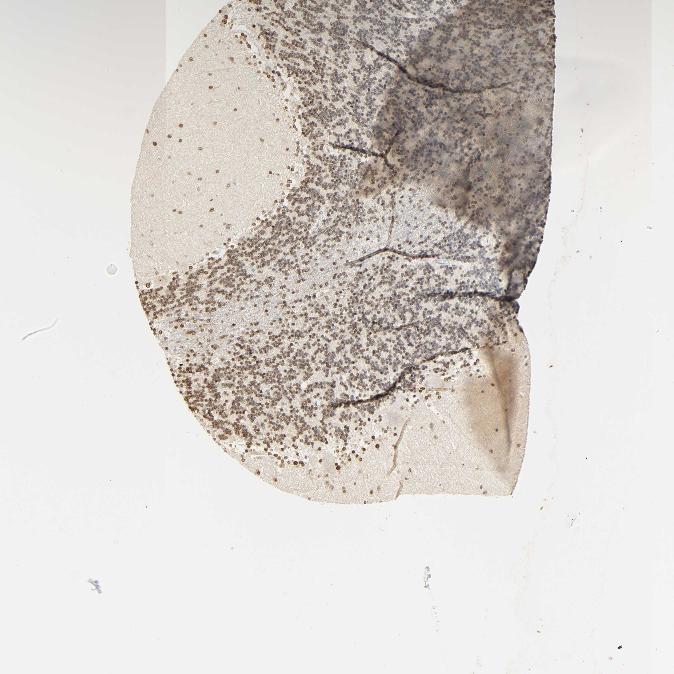

CEREBELLUM - Antibody stainingi

Antibody staining in the annotated cell types in the current human tissue is reported as not detected, low, medium, or high, based on conventional immunohistochemistry profiling in selected tissues. This score is based on the combination of the staining intensity and fraction of stained cells.

Each image is clickable and will lead to virtual microscopy that enables deeper exploration of all samples and also displays staining intensity scores, fraction scores and subcellular localization as well as patient and tissue information for each sample.

Antibody HPA041344Antibody HPA049132Antibody CAB000362Antibody CAB005419

Purkinje cells Not detectedMediumNot detectedNot detected

Cells in granular layer Not detectedHighNot detectedLow

Cells in molecular layer Not detectedHighNot detectedNot detected